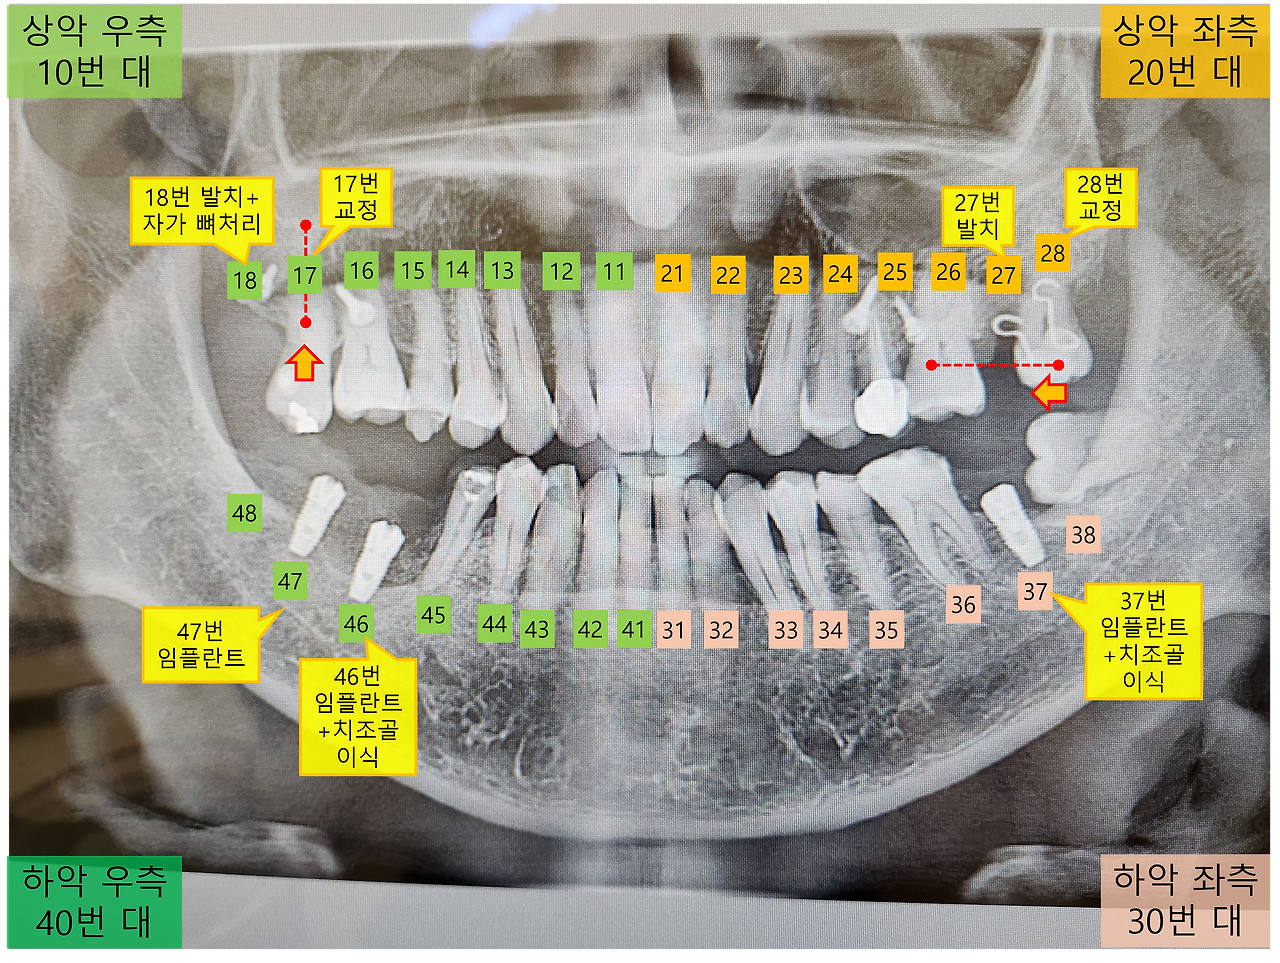

임플란트 2개 파노라마사진.png [큰 공사의 골격이 끝난 상태의 파노라마 사진]

이제 본격적으로 오른쪽 46번과 47번 위치에 임플란트 식립이 실시됩니다. 마스크를 얼굴에 덮으니 곧 시작될 식립작업에 대한 두려움이 서서히 밀려옵니다.

반면에 46번은 잇몸뼈가 부족해, 임플란트를 식립 전에 치조골과 콜라겐을 섞어서 넣는다고 하네요. 이렇게 하면 뼈의 재생을 촉진하고 수술 후 부작용을 줄이는데 도움이 될 수 있다고 하고, 또한 출혈도 동시에 잡을 수 있다고 하네요.

상당히 오랜 시간 동안 봉합작업이 진행되었습니다. 마침내 "고생하셨습니다"하는 말과 함께 드디어 임플란트 식립 수술이 모두 끝났습니다. 이제 식립이 잘 되었는지 확인하기 위해 파노라마 사진을 한번 더 촬영했습니다.

[46번과 47번 임플란트 식립 후 파노라마 사진]

의사분이 46번 부위의 잇몸뼈 손상이 심해, 치조골 이식도 많이 했다고 합니다. 이로 인해 이전 보다 붓기가 더 심해지고 피멍이 생길 수 있다고 하네요. 그리고 염증이 있었던 부위에는 혈관이 많이 형성되어 출혈이 많았지만, 치조골 이식 시 콜라겐을 함께 섞어 사용해 출혈을 막았기 때문에 큰 문제는 없을 것이라고 합니다.